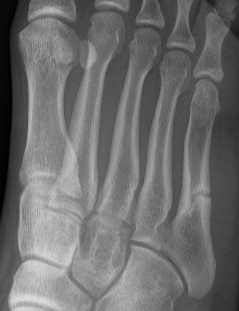

Base of 5th - Zone 1 / 2 / 3

Base Shaft Neck